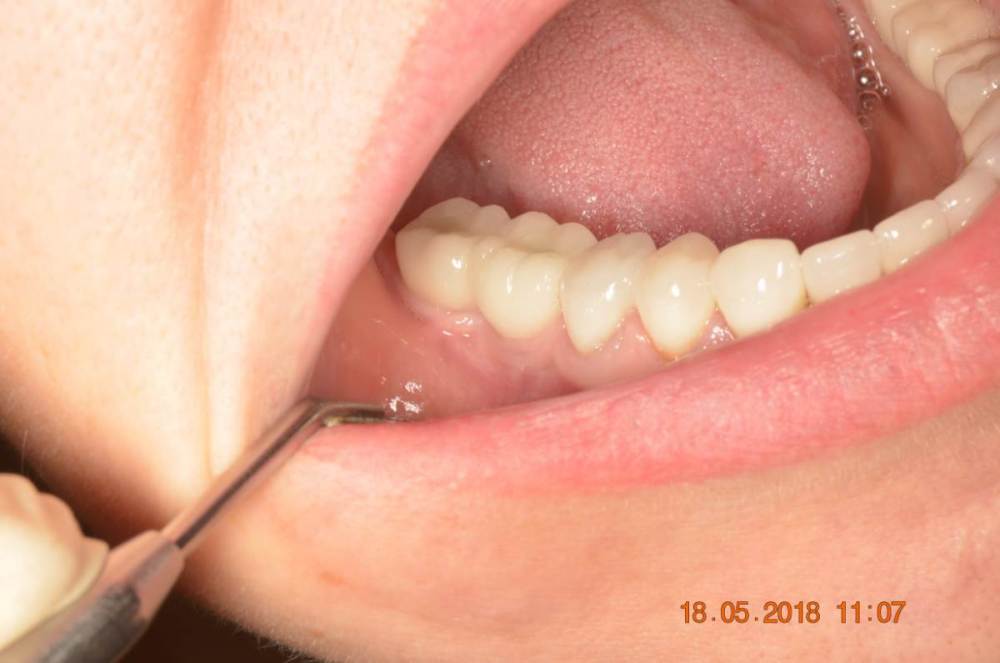

Большой Зеленый Опубликовано 7 ноября, 2022 Поделиться Опубликовано 7 ноября, 2022 Обратите внимание на даты 2 Ссылка на комментарий

Большой Зеленый Опубликовано 7 ноября, 2022 Поделиться Опубликовано 7 ноября, 2022 У дилера есть премил абатменты. За 10 лет работы проблем никаких не было. 1 Ссылка на комментарий